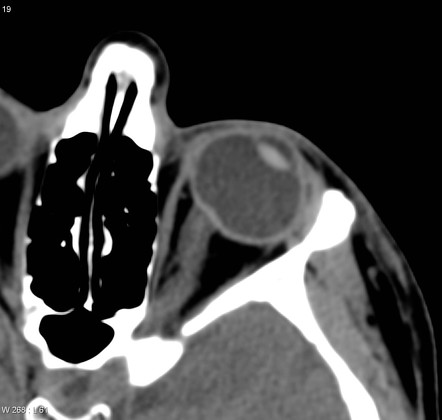

시신경유두에는 망막과, 이를둘러싸고 있는 맥락막, 가장 바깥쪽의 공막이 모두 모여있는 부위입니다.

가장 표면에 있는 부분이 바로 망막에 해당하는 부분이며, 수평으로 주해하던 망막신경섬유들이 안구 바깥을 향해 90도로 회전하게 됩니다.

안구를 빠져나가려고하는 망막신경섬유층(RNFL)이 시신경유두 전체부피의 90%를 차지 하게됩니다.

이부분을 사상판전층(Pre-laminar area)라고 합니다.

즉, 예상하다시피 바로 뒷부분에 사상판(lamina cribrosa) 라는 곳이 있습니다.

신경섬유들이 안구를 빠져나가는 곳에 있는 작은 세공(pore)가 수없이 많이 뚫려있는 판형태의 지역이 있는데,

이를 사상판(lamina cribrosa)라고 합니다.

이부분에는 직경 25~250um의 세공이 있고, 구멍주위에는 섬유성중격이 있고, 이를 도와주는 별아교세포(astrocyte)들이 존재합니다.

사상판 뒷부분에는 사상판후층(Retrolaminar region)이 있습니다.

이부분에는 사상판을 빠져나온 시신경섬유들이 주행하는 곳으로, 시신경 섬유들 주위에

마이엘린수초가 둘러싸이게되는 부분이며,